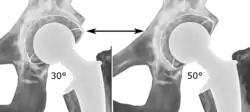

The direction of the acetabular cup influences the range of motion of the leg, and also affects the risk of dislocation.[16] For this purpose, the acetabular inclination and the acetabular anteversion are measurements of cup angulation in the coronal plane and the sagittal plane, respectively.

![Acetabular inclination.[95] This parameter is calculated on an anteroposterior radiograph as the angle between a line through the lateral and medial margins of the acetabular cup and the transischial line which is tangential to the inferior margins of the ischium bones.[95]](./Acetabular_inclination_of_hip_prosthesis.jpg)

![Acetabular inclination is normally between 30 and 50°.[95] A larger angle increases the risk of dislocation.[16]](./Range_of_acetabular_inclination.png)